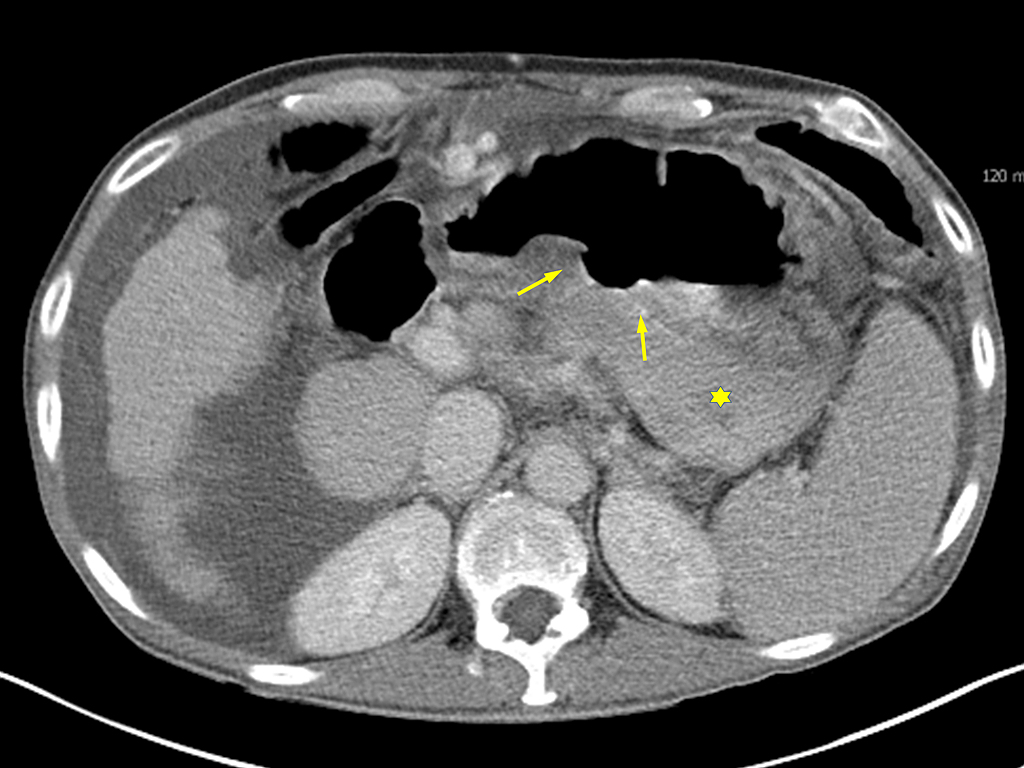

Perforation du tube digestif

. Image TDM en coupe axiale se donne la presence de

air libre a l' espace superieur de l'abdomen . Le

diagnostic est vers estomac et duodenum

par la presence des petites bulbes d'air intra

parietale . |

Diagnostic d'ulcere perfore sur la

TDM se verifie quand : la presence de

pneumoperitoine , epaissisement irregulie de la

paroi duodenale ou gastrique , bulbe d'air intra

parietale , infiltration graisseuse mesentrique et

epanchement liquidienne intra peritoneal |

La presence des petits bulbe

d'air intra parietale posterieure : ulcere de la

face posterieure perfore |

Ulcere gastro duodenal perfore : Image

TDM en coupe axiale |